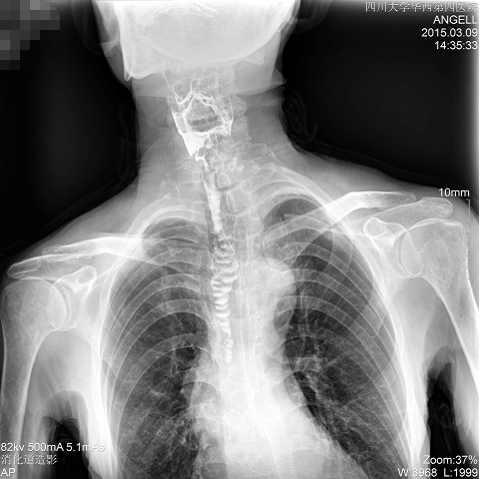

如下圖所示:該患者因吞咽時感到很難受,進食時也經常咳嗽故就醫診斷。使用多功能dr為病人進行消化道造影診斷,要求他吞鋇后發現,食道各段通過順利,形態規則,雙側梨狀窩不對稱左側稍淺,多次吞咽動作后,仍見鋇劑滯留,并見鋇劑進入氣管,屬于會厭征陽性。會厭功能紊亂,鋇劑進入了氣管。

圖為正位:通過動態影像可以清楚看到鋇劑進入了支氣管道且雙側梨狀窩不對稱

圖為斜位:通過動態影像可以清楚看到鋇劑進入了支氣管道

通過多功能dr可以診斷該病人的癥狀為會厭功能紊亂,鋇劑進入到了氣管。而在動態透視下可以清晰的觀察到鋇劑從何處進入氣管,可清晰顯示食管粘膜結構。使用多功能dr其獨特的視頻采集技術,可實時保存視頻并能實現900萬像素實時點片,才能獲取這樣清晰的病灶點。而常規dr只能拍攝靜態片,且成像效果大打折扣,因此較難確診病灶。